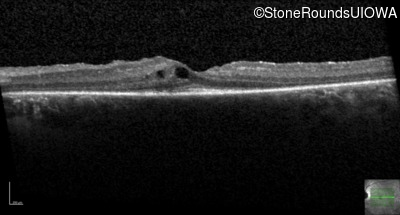

Optical Coherence Tomography - Right -

20/20 -1

Exemplar / OCT Stack